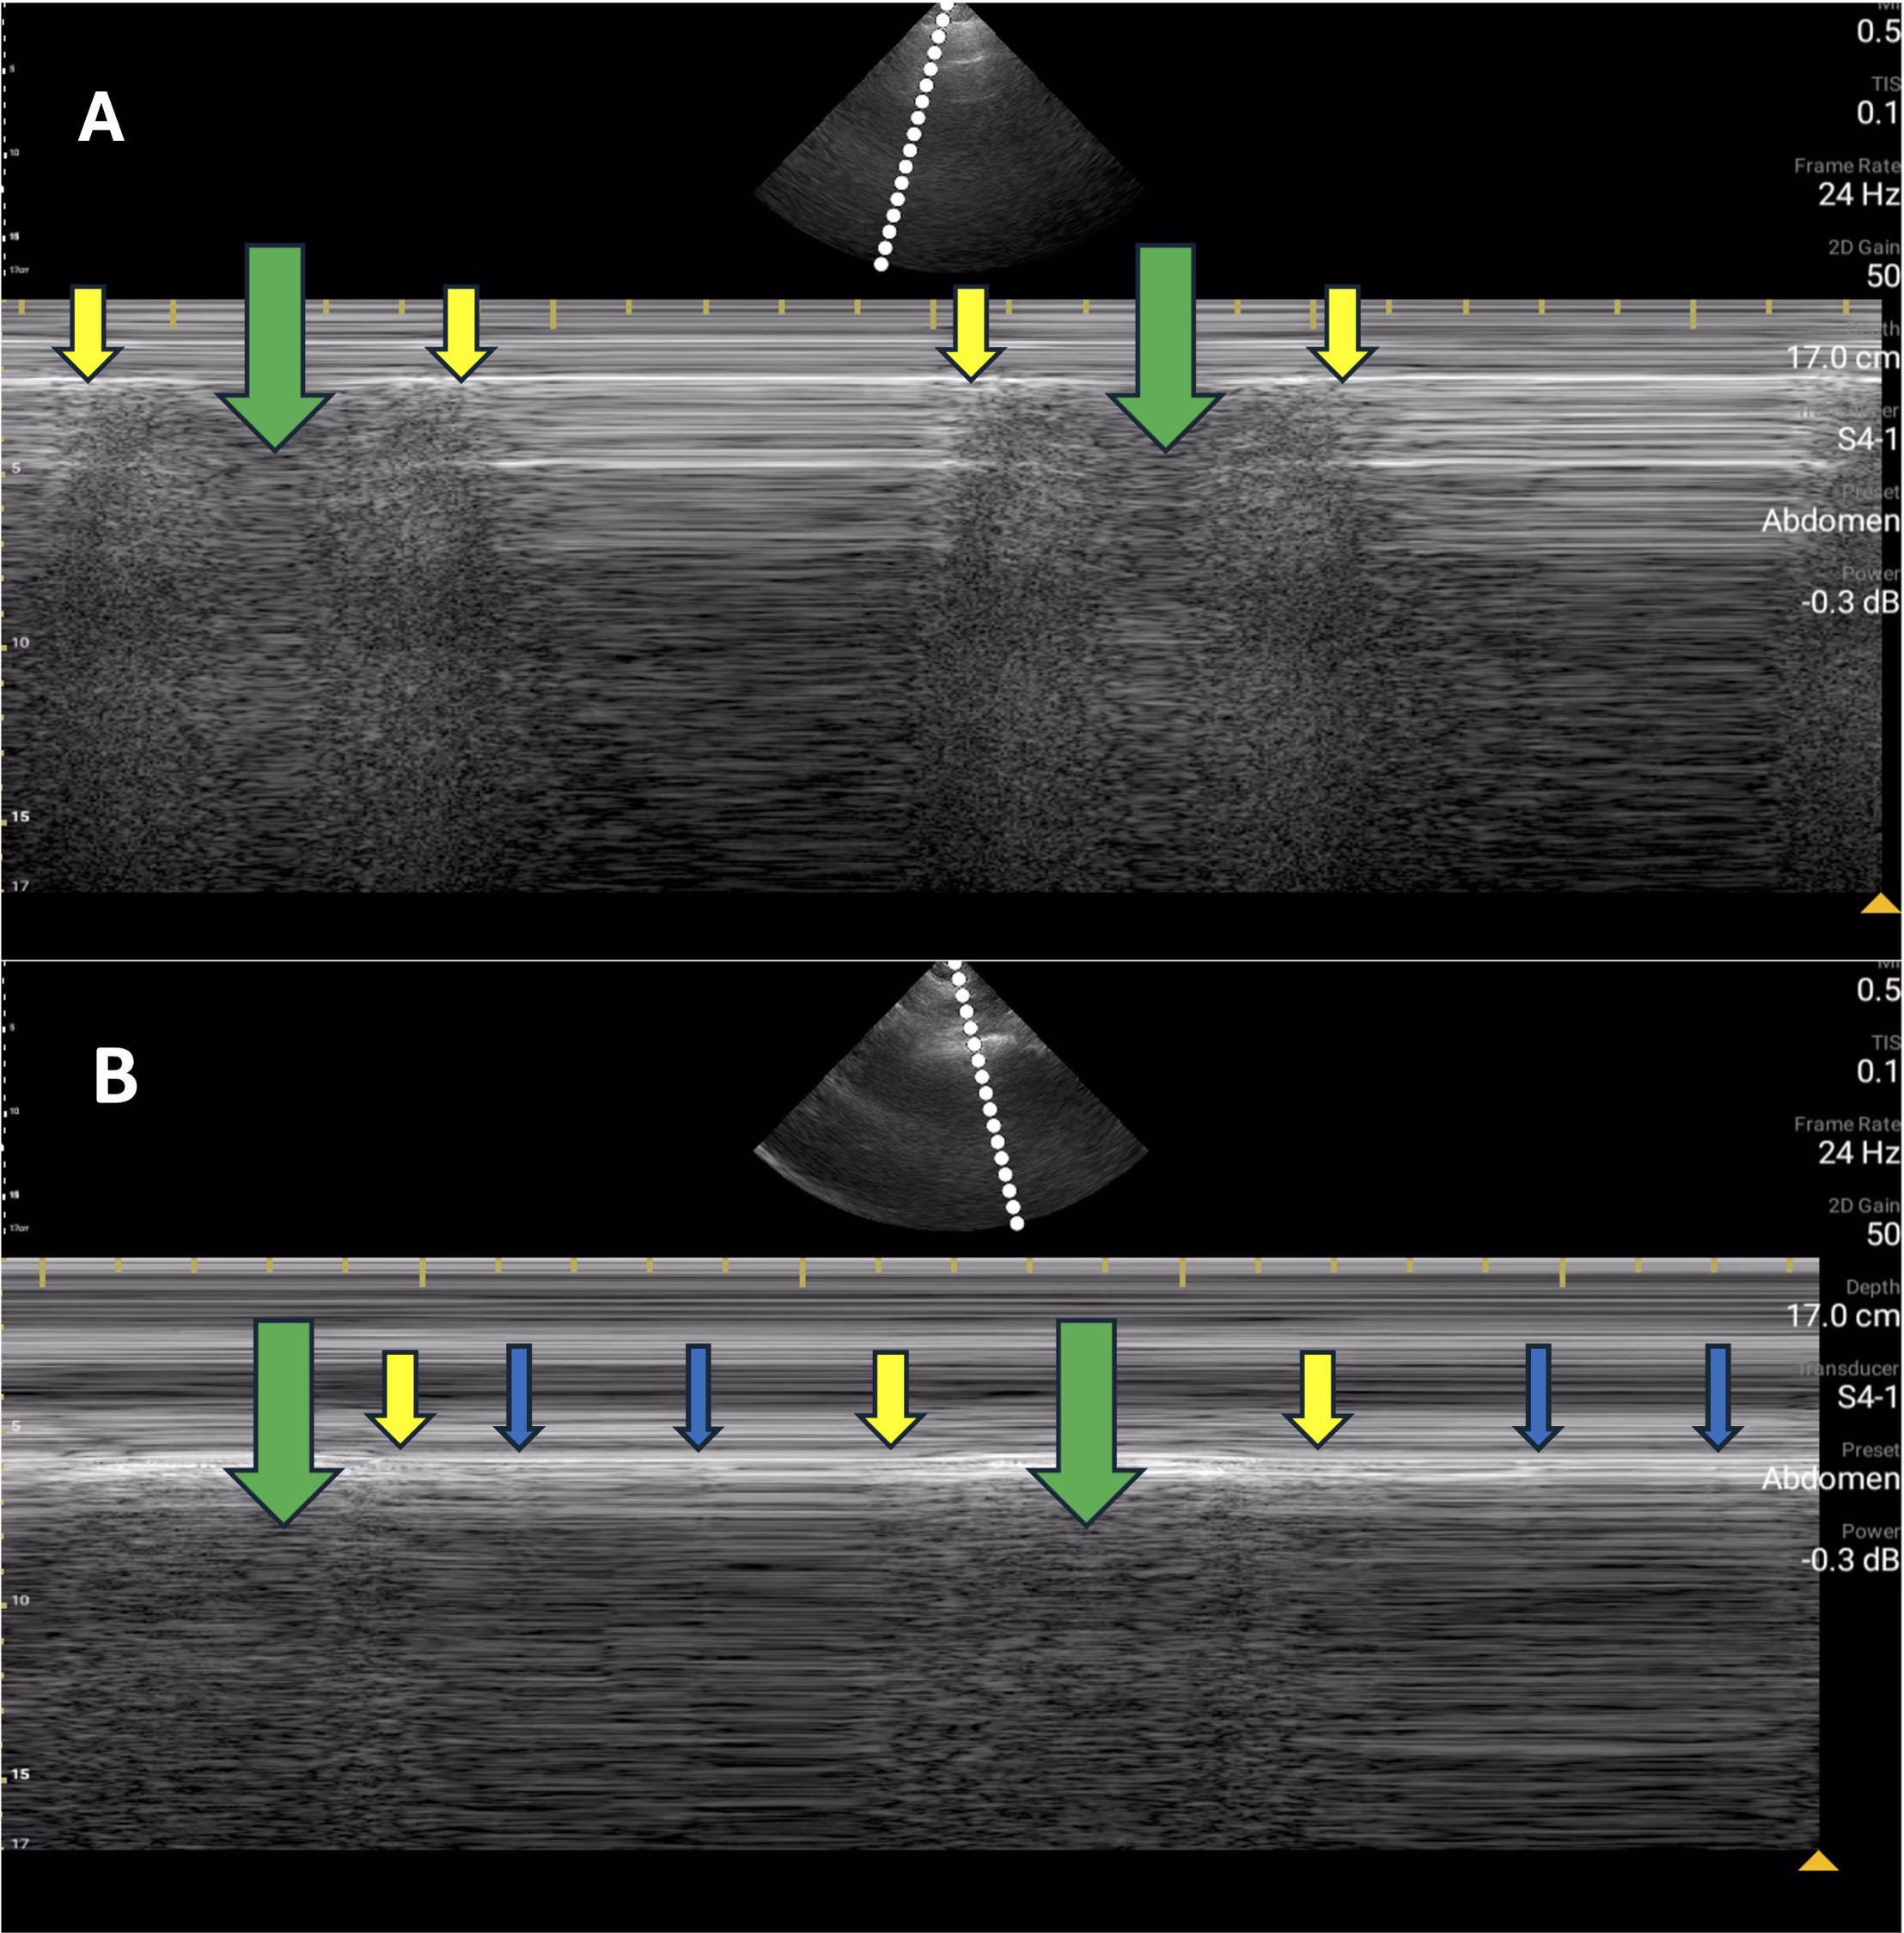

Peritoneal Volume Influence on POCUS Volume Assessment in Patients Undergoing Peritoneal Dialysis

María Muñiz Rincón; Diego Barbieri, MD; Virginia López de la Manzanara; Elena Ruiz Ferreras; Arianne Aiffil Meneses; Carlos Fernández Fernández; Cristina Riaza Ortiz; Rómulo Loayza López; Jose Antonio Herrero Calvo; Ana I. Sanchez-Fructuoso - This study investigates variations in fluid overload using point of care ultrasound (POCUS). It assesses patients undergoing peritoneal dialysis (PD) with [...]